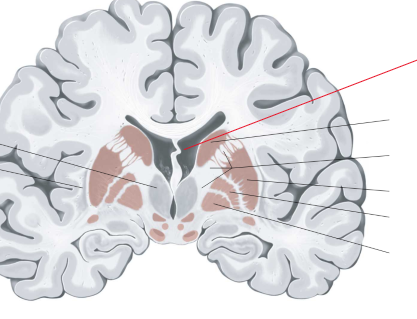

nucleus caudatus

putamen

globus pallidus

capsula interna (corona radiata)

capsula externa

capsula extrema

hippocampus

amygdala

fornix

laterale ventrikels (I en II)

septum pellucidum